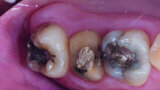

Fig. 14a: Clinical image: Pre-op.